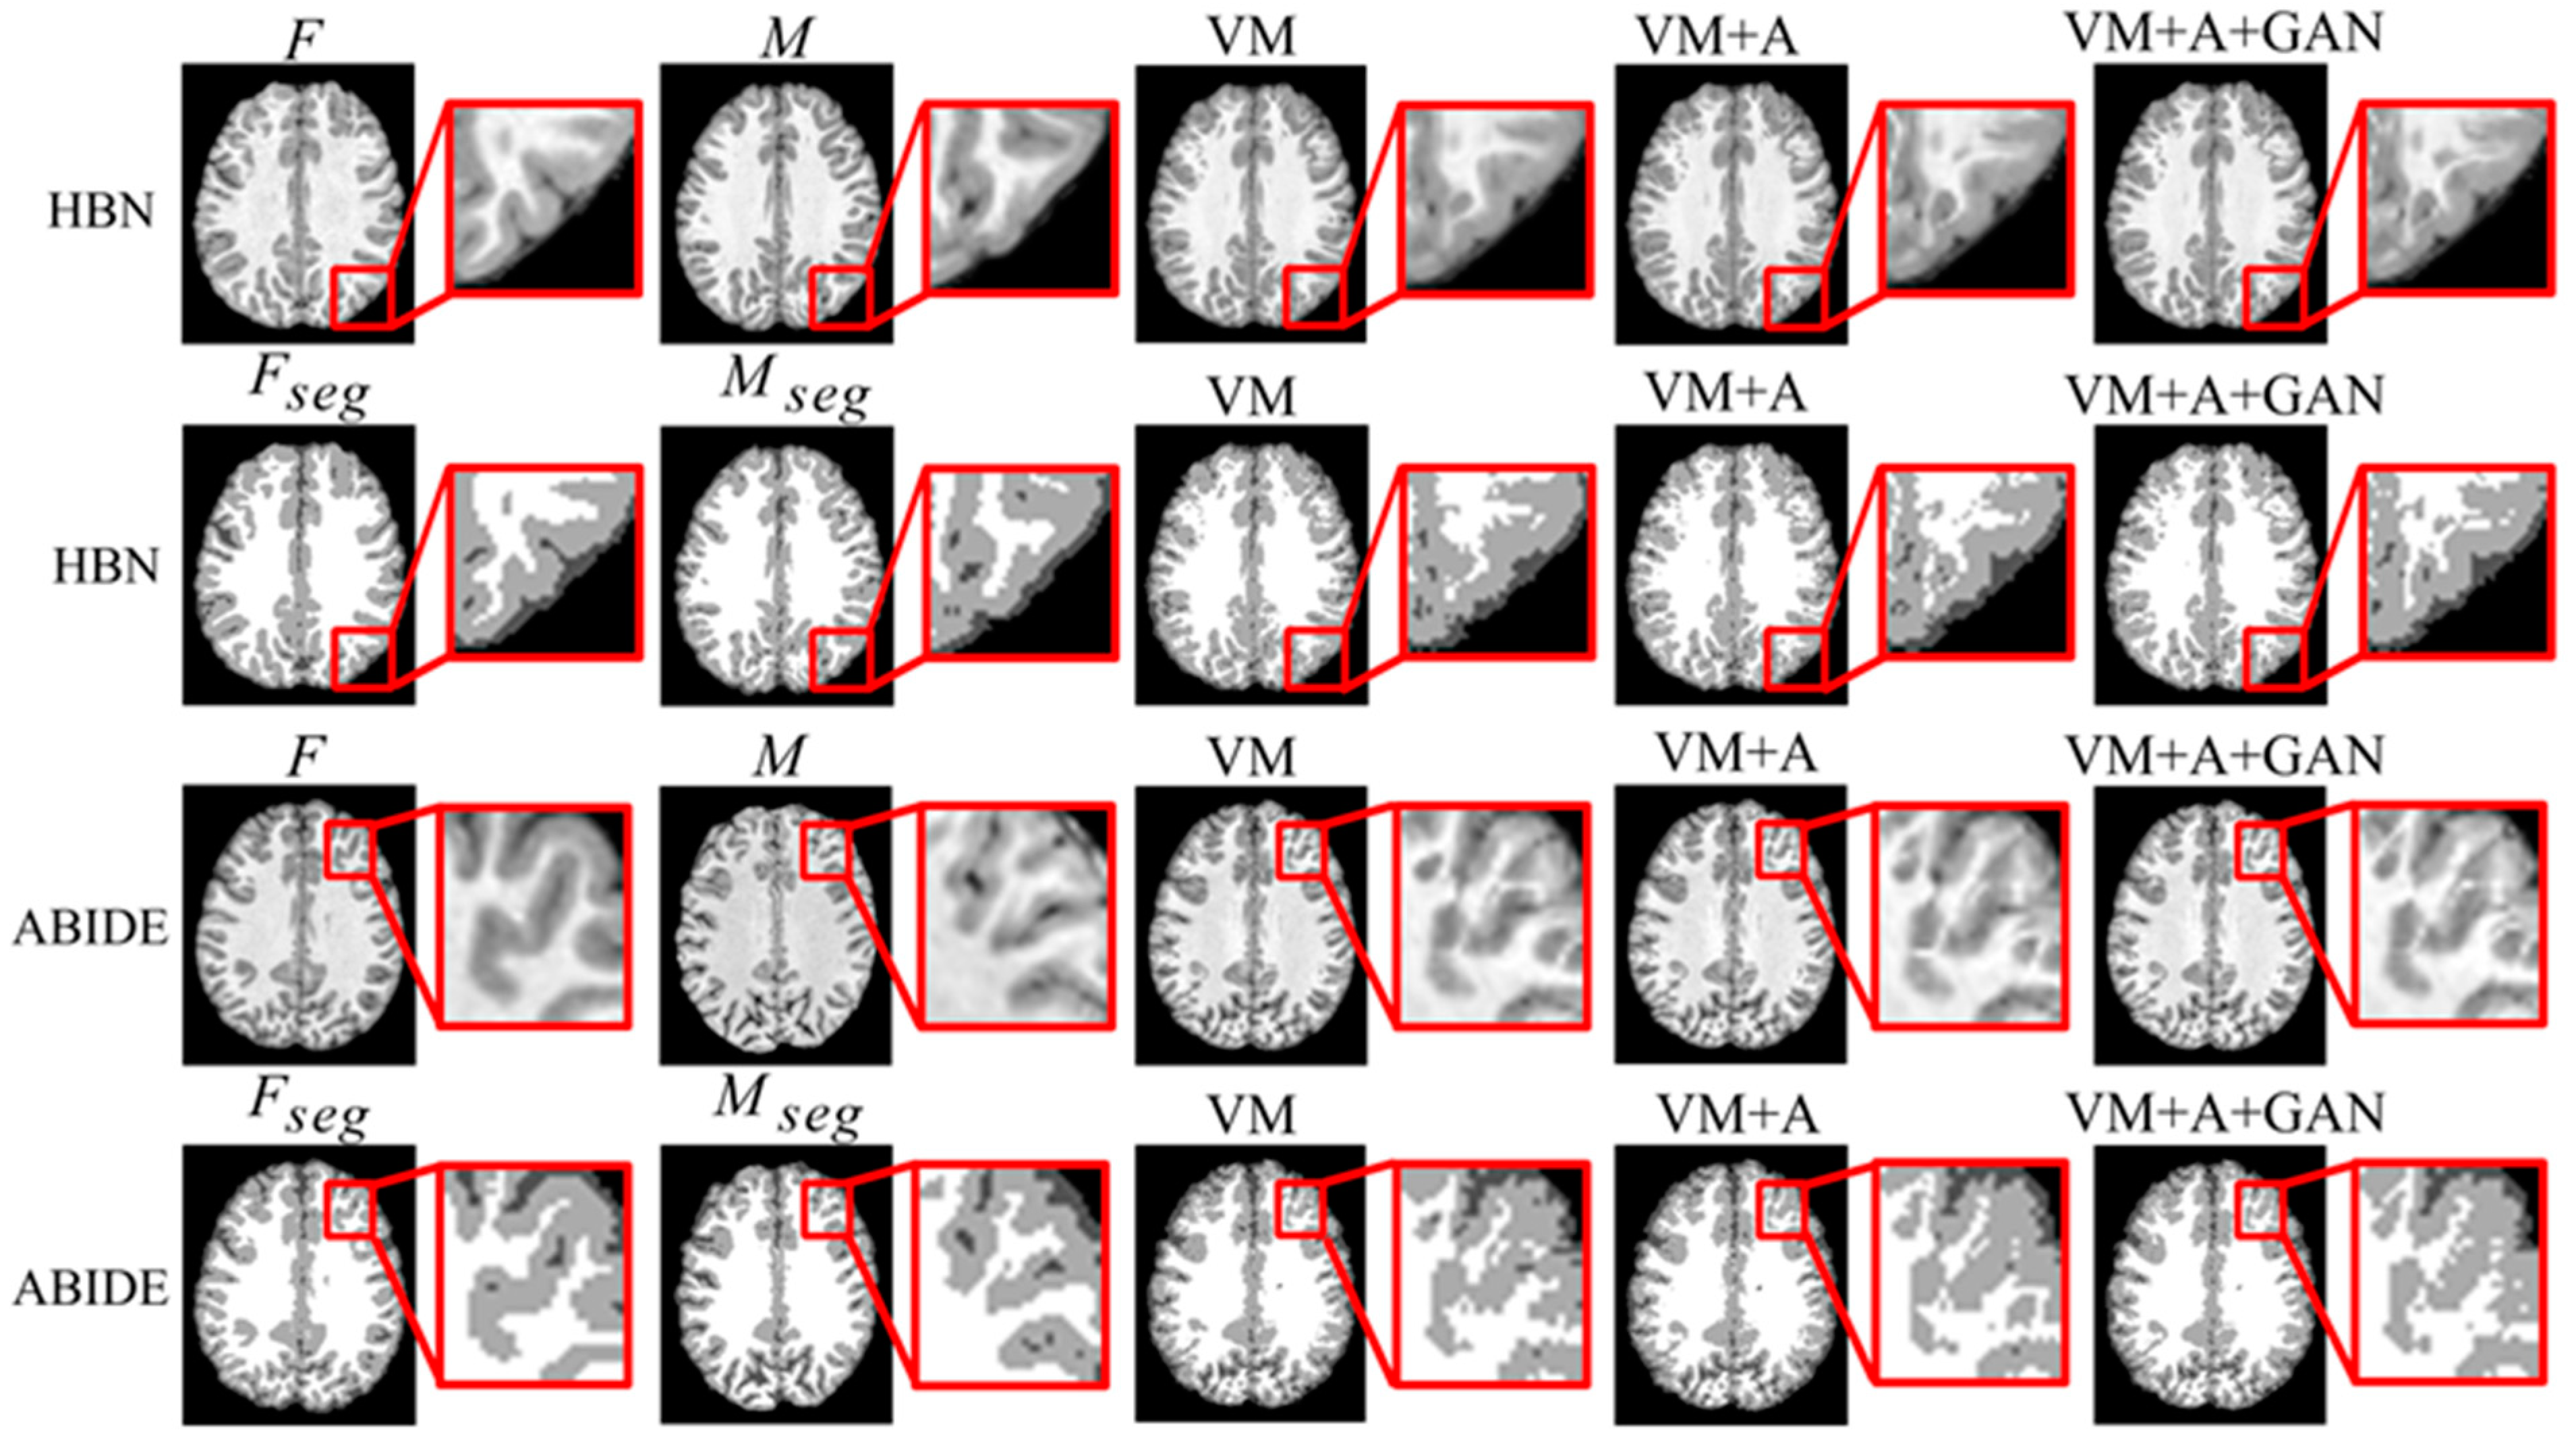

Second, the proposed GAN method is compared with the VM and VM + A methods. Figure 4 shows the registered moving image and the fixed image. Moreover, the first row represents the original image from the HBN dataset, and the second row represents the segmentation image corresponding to the original image from the HBN dataset. Similarly, the third row represents the original image from the ABIDE dataset, and the fourth row represents the segmentation image corresponding to the original image from the ABIDE dataset. Additionally, the enlarged figure on the right shows that the result for the proposed method regarding the training of the registration, augmented, and discrimination networks together is closer to the fixed image. Through the experimental results, the performance of the registration, augmented, and discrimination networks when trained together is verifiably better than that of the registration network trained individually and of the registration and augmented networks trained simultaneously.

Figure 4.

Registration results based on deep learning methods. Among them, VM represents the result obtained by the VoxelMorph method, VM + A represents the result obtained by training the registration network and the enhanced network together, and VM + A + GAN represents the result obtained by our method.